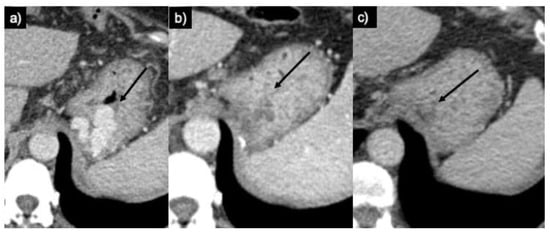

2. Results

3.2. Technique

3.2.1. PARTO

3.2.2. CARTO